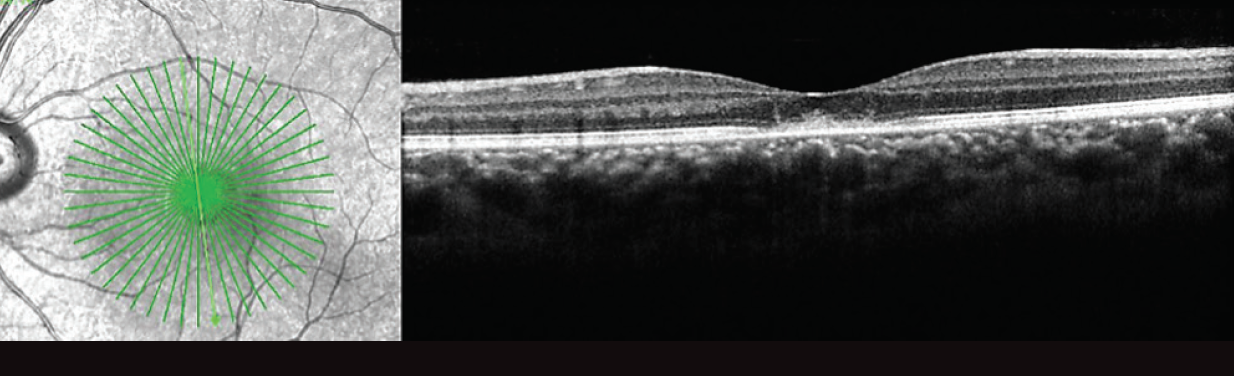

Figure 7. OCT 6 months after presentation shows a return to baseline OS with a focal outer retinal defect consistent with the patient’s prior diagnosis of solar retinopathy. There has been restoration of the remaining ellipsoid zone and resolution of the subretinal hyperreflective material that was noted on the earlier scan.

When the patient returned for follow-up 1 week later, her visual acuity had improved to 20/60 OS without intervention. She was asked to return in 1 month but did not return until 6 months later, at which time her visual acuity had improved to 20/30 OS. On funduscopic exam, the central yellow lesion had improved (Figure 6). The patient’s OCT returned to baseline OS and was notable only for the focal outer retinal defect symmetric with her other eye and stable from her exam 3 years earlier (Figure 7).

The case described here demonstrates classic OCT findings seen in UAIM, with heterogeneous hyperreflective thickening at the level of the outer retina and RPE resulting in disruption of the ellipsoid layer.3,4 On OCT at follow-up, the outer retinal layers were restored, which corresponded with visual recovery.